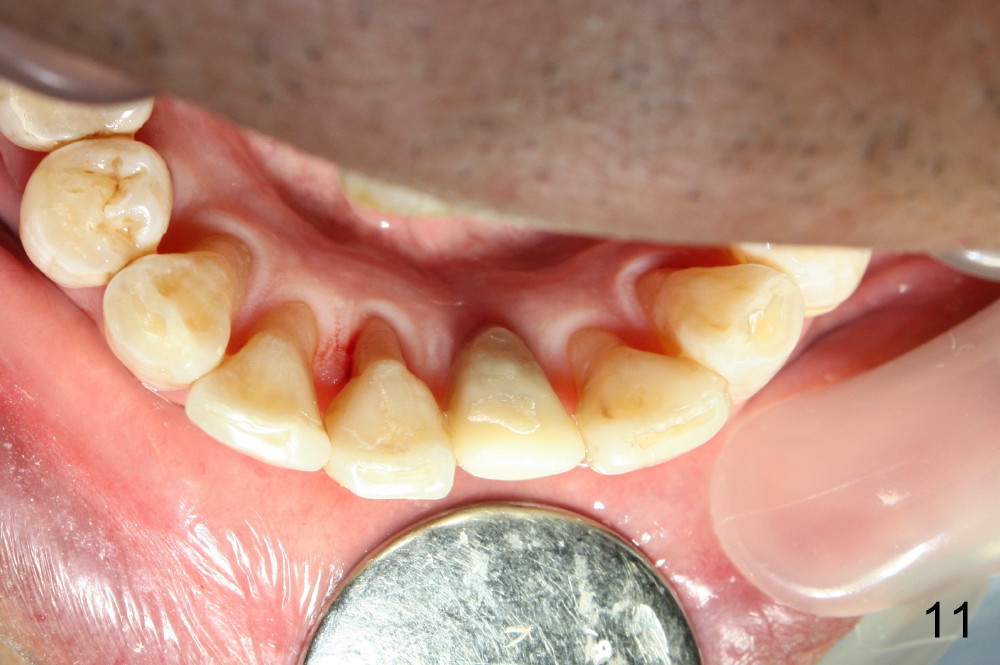

Fig.10,11 show 7 day follow up.  The permanent crown is seated 4.5 months postop (Fig.12).  Minimal bone resorption occurs at the crest 4 months postop (Fig.13), which is most likely associated with conservative approach (flapless).  The patient returns for follow up 2.5 months post cementation (Fig.14,15).  The implant remains in the bone 4 years post cementation (Fig.16 CT coronal section; lingual thread exposure, corresponding to preop defect in Fig.1).   There is mild coronal bone resorption 5 years 4 months post cementation (Fig.17).